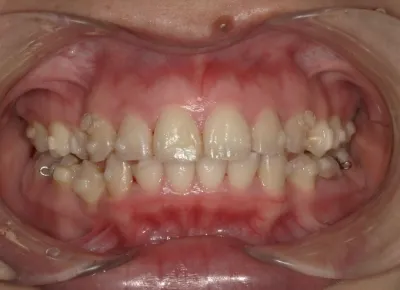

Before

After

治療期間

費用総額